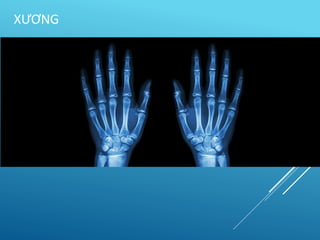

• Xương khớp:

– Dấu biến dạng

– Điểm đau chói

– X quang (Thẳng, nghiêng, 3 tư thế).

X QUANG THẲNG, NGHIÊNG